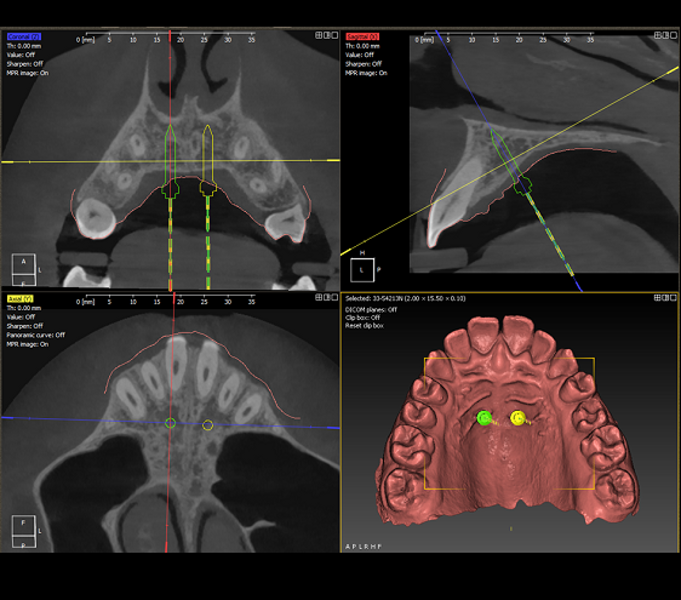

DDS-Pro enables precise planning, guided implantation and appliance design in orthodontics by integrating CBCT data and intra-oral scans into a streamlined digital workflow. (All images: Polorto)

1. capture and analysis of the CBCT scan and intra-oral scan to determine optimal mini-implant placement in line with anchorage needs and appliance design;

2. creation of surgical guides for precise implantation;

DDS-Pro software (Polorto) supports both the two-stage and single-stage approaches. However, the single-stage method eliminates implant position discrepancies commonly encountered in the two-stage workflow. It also significantly enhances installation accuracy, improving reproducibility and eliminating the need for additional appointments or chairside adjustments.

Once 3D planning has been completed, mini-implants can be placed with high precision, independent of the operator’s manual skill. The appliance, anchored to these implants, functions exactly as designed.